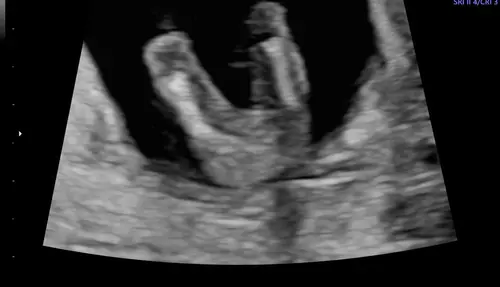

Ik heb geen potty shot meer van ons zoontje, die wordt bijna 2, maar wel van ons tweede kindje waarvan ik denk dat dat een meisje is:

9 maanden geleden